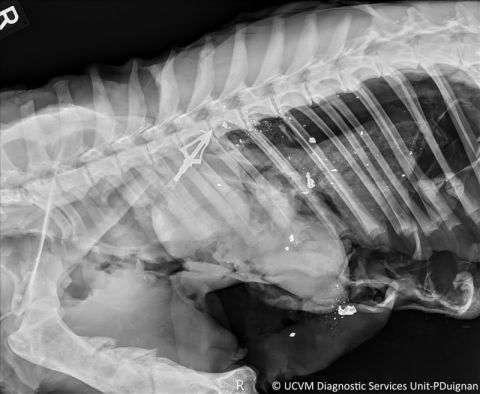

Dog: Peritoneum. Hemoabdomen due to splenic hemangiosarcoma.